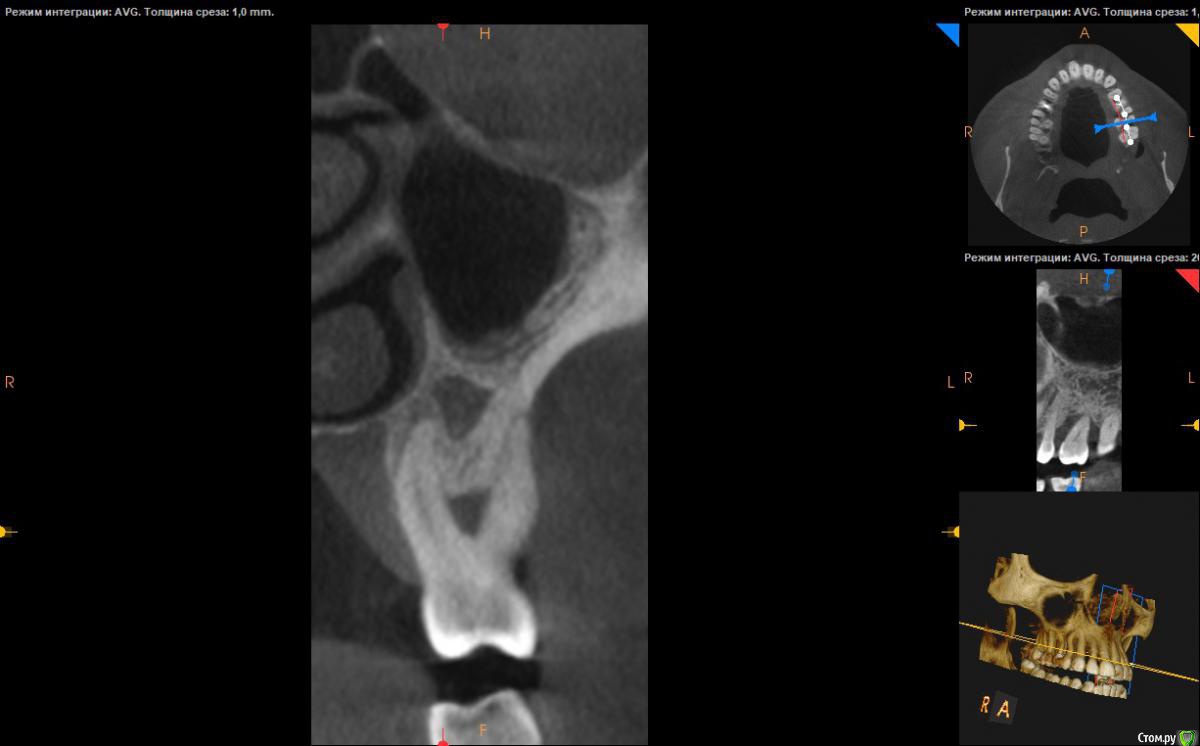

Neilrus Опубликовано 14 января, 2019 Поделиться Опубликовано 14 января, 2019 Добрый вечер, коллеги, посмотрите срез, пожалуйста, планирую одномоментно установить импл, смущает полость в толще кости под пазухой, с ней никак не связана. смело ставить сквозь нее и под пазуху? Высота 12мм, думал установить 11мм и прошить ее насковозь.Вопрос в том что за полость и как действовать правильнее, с таким не сталкивался в своей хирургии, хотя многокамерные пазухи видел ни раз.Как вариант если там слизистая как в пазухе тотально ее выскрести и заполнить графтом?Спасибо ) Ссылка на комментарий

Ethan Hunt Опубликовано 15 января, 2019 Поделиться Опубликовано 15 января, 2019 может я не понял информацию..12 мм это высота чего? Расстояние от крестальной части гребня до пазухи? Ссылка на комментарий

Neilrus Опубликовано 15 января, 2019 Автор Поделиться Опубликовано 15 января, 2019 может я не понял информацию..12 мм это высота чего? Расстояние от крестальной части гребня до пазухи?да Ссылка на комментарий

Дмитрий Л. Опубликовано 15 января, 2019 Поделиться Опубликовано 15 января, 2019 Покрутите срезы еще разочек, думаю найдете связь либо с гайморовой либо с зубом 3 Ссылка на комментарий

Данилова Опубликовано 17 января, 2019 Поделиться Опубликовано 17 января, 2019 А это не гранулема? Ссылка на комментарий

___49___ Опубликовано 21 января, 2019 Поделиться Опубликовано 21 января, 2019 (изменено) А это не гранулема?нет ), у септы больше шансов . Изменено 21 января, 2019 пользователем ___49___ Ссылка на комментарий